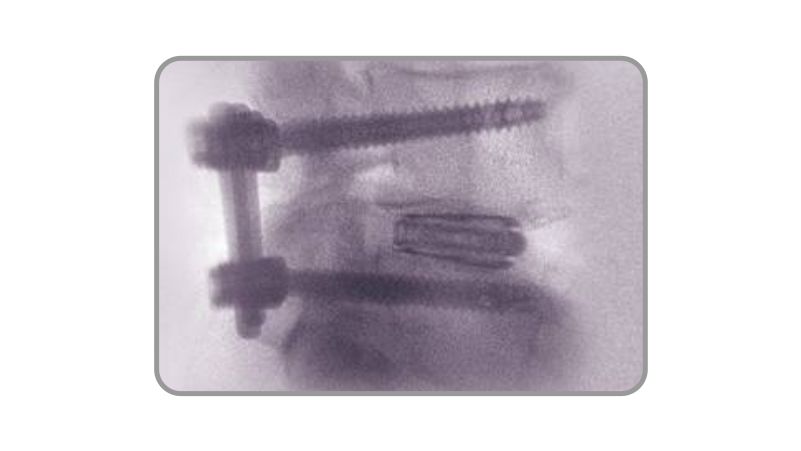

Hanfuse é um dispositivo estéril de fusão lombar expansível (8–13 mm) para distração controlada e ajuste às placas terminais, indicado no tratamento da doença degenerativa do disco entre L2–S1 (1–2 níveis).

Aplicável para as abordagens: PLIF, TLIF, MISS-TLIF e ENDOLIF.